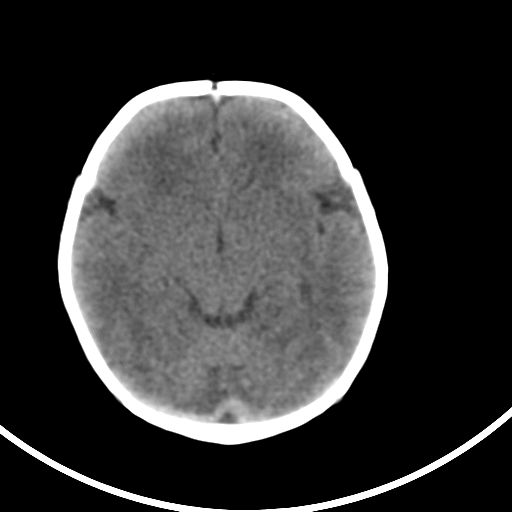

新生儿3天,超过预产期5天剖宫产,有缺氧病史,具体评分不详,现反应差,肌张力低,前囟平,原始反射存在,无苦闹等。

正常颅脑表现。

kaolv小脑幕,后纵裂区蛛网膜下腔出血;轻度脑肿胀

矢状窦旁征——支持蛛网膜下腔出血